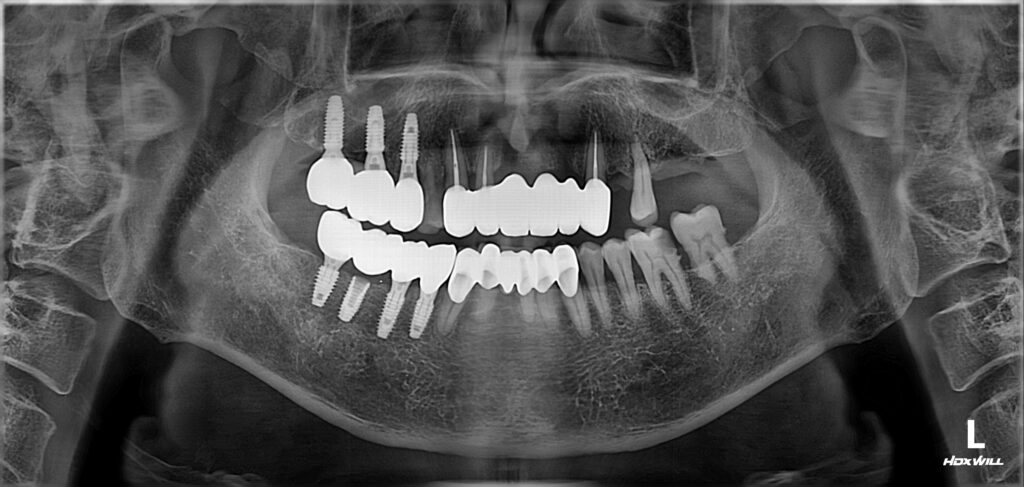

오늘은 인접면 충치 이맥스 인레이로 치료한 사례를 가져왔습니다. 치아에 까만 점 같은 게 보여서 충치치료받기 위해 치과에 오시는 분들이 종종 있습니다. 하지만 실제로 치아 교합면(씹는 면)에 까맣게 보이는 점들은 빠르게 진행하는 충치보다는 매우 느리게 진행하거나 혹은 진행을 멈춘 정지성 우식인 경우가 많아요. 그래서 그것은 무서워할 필요가 없는데 오히려 복병은 따로 있습니다. 바로 치아 사이 충치(인접면 충치)입니다. 왜냐면 인접면 충치는 자칫하면 놓칠 수도 있기 때문이에요. 오늘 인접면 충치를 이맥스 인레이로 치료한 사례 보면서 더 상세한 얘기 해볼게요. 충치 없는지 궁금해요. 30대 여성분이 검진차 내원하셨습니다. 혹시 충치로 의심되는 치아가 보이시나요? 노란색 화살 표시한 갈색 점들은 사실 아주 초기에서 정지된 정지성 충치로 보입니다. 따라서 이것들은 별로 위협이 되진 않습니다. 진짜 조심해야 할 충치는 바로 연두색 화살 표시 부분입니다. 연두색 화살 표시 부분을 잘 보시면 까맣게 비춰 보이는 것을 확인할 수 있죠. 치아 사이 충치 = 인접면 충치라고 하고요 꽤나 깊은 충치이며, 방치 시 일이 커지는 그런 무서운 충치입니다. 인접면 충치 발견과 치료 계획 엑스레이에도 연두색 화살 표시 해둔 부분 잘 봐보세요. 까맣게 보이죠. 해당 부위를 가장 잘 확인하는 방법은 교익 방사선 촬영입니다. 바이트 윙이라고도 하는 촬영 기법인데요. 인접면 충치를 정확하게 확인할 수 있습니다. 교익 방사선 엑스레이 치아는 가장 바깥쪽에 법랑질이라는 (흰색 실선 그림) 가장 단단한 조직이 둘러싸고 있고 그 안에는 상아질이라는 다소 무른 조직으로 되어있는데 충치가 법랑질 안에만 있을 때는 위협적이지 않다가,법랑질을 지나쳐 상아질로 진행되면 충치가 급격하게 진행될 수 있습니다. 늦지 않게 잘 치료해야 하죠. 이맥스 인레이로 인접면 충치 치료하다. 제가 가장 선호하는 이맥스 인레이로 치료하기로 했습니다.(세라믹 인레이를 만드는 회사가 여러군데인데, 이보클라라는 회사에서 만든 세라믹을 이맥스라고 부릅니다.) 기존에 충치치료가 되어있던 치아라서 그것들을 모두 깔끔하게 제거하고 치아 사이 충치도 모두 제거하고 이맥스 인레이로 수복했습니다. 이맥스 인레이란?(세라믹 인레이) –> https://brplant.co.kr/2772/ 교합조정을 하고(물리는 관계를 조절) 거친 부분을 다듬어주면 치료는 끝이 납니다. 때로, 충치가 예상외로 깊어서 신경치료나 mta 치료가 동반되는 경우가 있는데, 다행히 충치가 깊지 않아서 신경치료나 mta 치료는 필요 없었습니다 아래는 mta를 이용하여 신경치료를 피하기 관련 내용 정리한 글 입니다. –> https://brplant.co.kr/2942/ 마무리하며 위에서도 언급했듯 교합면 충치보다 인접면 충치가 더욱 위험합니다. 그런데 인접면 충치는 발견하기 어려운 경우가 있어서 방치된 채 충치가 많이 진행되는 경우가 때때로 있습니다. 그렇기 때문에, 검진을 꼼꼼하게 해주는 치과에 주기적으로 검진을 다녀야 하는 것입니다.